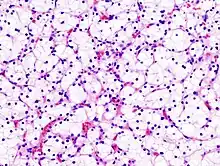

| Micrograph of the most common type of renal cell carcer (clear cell)—on right of the image; non-tumour kidney is on the left of the image. Nephrectomy specimen. H&E stain | |

The gross and microscopic appearance of renal cell carcinomas is highly variable. The renal cell carcinoma may present reddened areas where blood vessels have bled, and cysts containing watery fluids.[58] The body of the tumour shows large blood vessels that have walls composed of cancerous cells. Gross examination often shows a yellowish, multilobulated tumor in the renal cortex, which frequently contains zones of necrosis, haemorrhage and scarring. In a microscopic context, there are four major histologic subtypes of renal cell cancer: clear cell (conventional RCC, 75%), papillary (15%), chromophobic (5%), and collecting duct (2%). Sarcomatoid changes (morphology and patterns of IHC that mimic sarcoma, spindle cells) can be observed within any RCC subtype and are associated with more aggressive clinical course and worse prognosis. Under light microscopy, these tumour cells can exhibit papillae, tubules or nests, and are quite large, atypical, and polygonal.

Recent studies have brought attention to the close association of the type of cancerous cells to the aggressiveness of the condition. Some studies suggest that these cancerous cells accumulate glycogen and lipids, their cytoplasm appear "clear", the nuclei remain in the middle of the cells, and the cellular membrane is evident.[59] Some cells may be smaller, with eosinophilic cytoplasm, resembling normal tubular cells. The stroma is reduced, but well vascularised. The tumour compresses the surrounding parenchyma, producing a pseudocapsule.[60]

The most common cell type exhibited by renal cell carcinoma is the clear cell, which is named by the dissolving of the cells' high lipid content in the cytoplasm. The clear cells are thought to be the least likely to spread and usually respond more favourably to treatment. However, most of the tumours contain a mixture of cells. The most aggressive stage of renal cancer is believed to be the one in which the tumour is mixed, containing both clear and granular cells.[61]